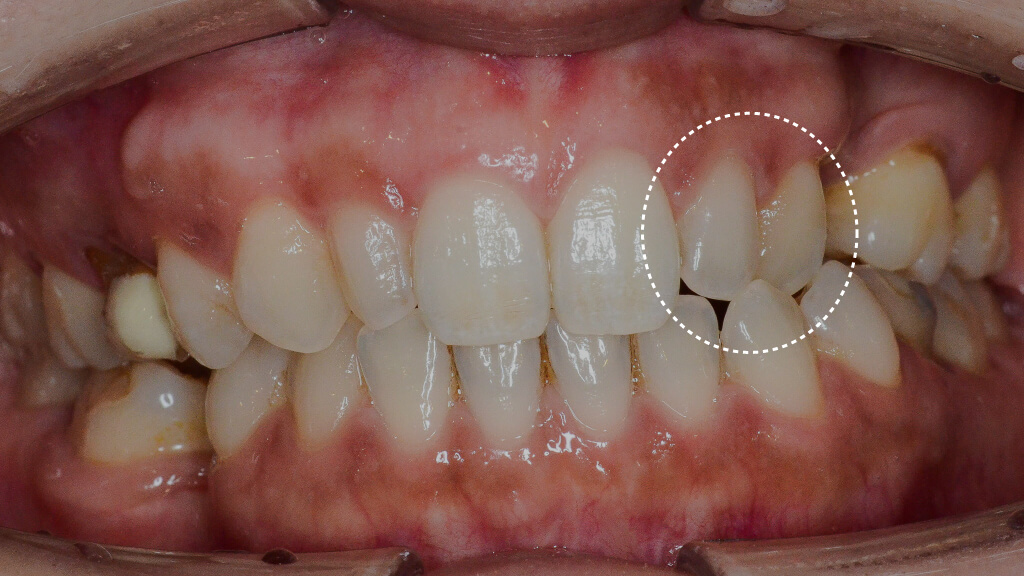

2.術前正面

さらに歯並びの問題として、左上の2番・3番の歯が下の歯よりも内側に位置している「クロスバイト(反対咬合)」の状態でした。

4.術前正面クロスバイト

このように、「歯の欠損」「歯並びの問題」「噛み合わせの問題」が複合的に関係しているケースでは、矯正治療とインプラント治療を組み合わせた包括的な治療が必要になります。

左上1番・2番の歯は、治療前には下の歯より内側に入ってしまうクロスバイト(反対咬合)の状態でしたが、インビザラインによる矯正治療によって歯の位置関係が改善し、かみ合わせも整ってきました。

7.術前左1年経過比較

また、矯正治療によってインプラントを埋入するためのスペースもしっかり確保できたため、このタイミングでインプラントの埋入手術を行います。